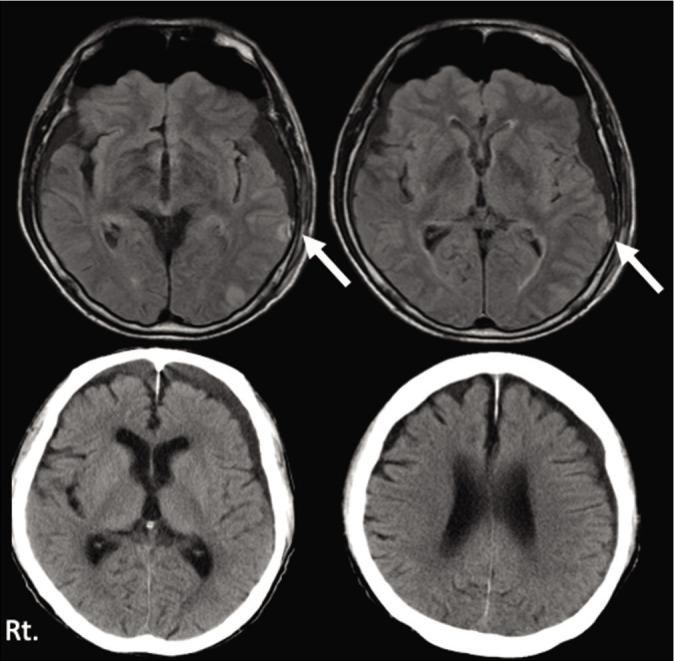

A 73-year-old man fell at night, and visited a former medical institution by himself. No abnormal neurological finding was detected. Head computed tomography (CT) detected no abnormal finding. He was diagnosed minor head injury and was hospitalized at midnight and discharged after brain magnetic resonance image (MRI) next day. Brain MRI also detected no abnormal findings. Three days later, he visited our hospital himself, because of the severe headache. Neurologically, he had a mild consciousness disturbance and head CT revealed left ASDH. We performed endoscopic evacuation of hematoma under local anesthesia. Then, the clot was evacuated under the endoscopic procedure through dilated burr hole and pulsatile bleeding from the cortical artery was observed, which was considered to be the source of the ASDH. The patient's consciousness disturbance was improved immediately after surgery and he discharged without neurological deficit.

一名73岁男性夜间摔倒,自行前往之前的医疗机构就诊。未发现异常神经学体征。头部计算机断层扫描(CT)未发现异常。他被诊断为轻度头部损伤,于午夜住院,并在次日进行脑磁共振成像(MRI)后出院。脑MRI也未发现异常。三天后,他因严重头痛自行前来我院就诊。神经学检查发现他有轻度意识障碍,头部CT显示左侧急性硬膜下血肿。我们在局部麻醉下进行了内镜血肿清除术。然后,在内镜操作下通过扩大的骨孔清除血凝块,并观察到来自皮质动脉的搏动性出血,这被认为是急性硬膜下血肿的出血源。患者术后意识障碍立即改善,出院时无神经功能缺损。